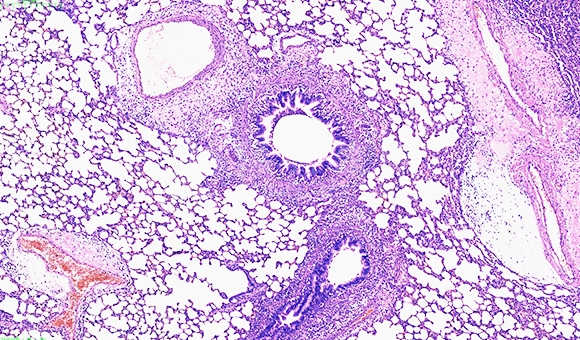

病理分析

病理分析是探讨器官、组织或细胞所发生的疾病过程,探讨病变产生的原因、发病机理、病变的发生发展过程,最后做出病理诊断。染色针对不同的

病理分析是探讨器官、组织或细胞所发生的疾病过程,探讨病变产生的原因、发病机理、病变的发生发展过程,最后做出病理诊断。染色针对不同的组织情况,通过观察空白组及实验组不同的染色结果来确认病变情况,也可以通过软件来计算病变组织(染色部位)的面积比例。

1 HE病理分析 HE染色病理描述分析